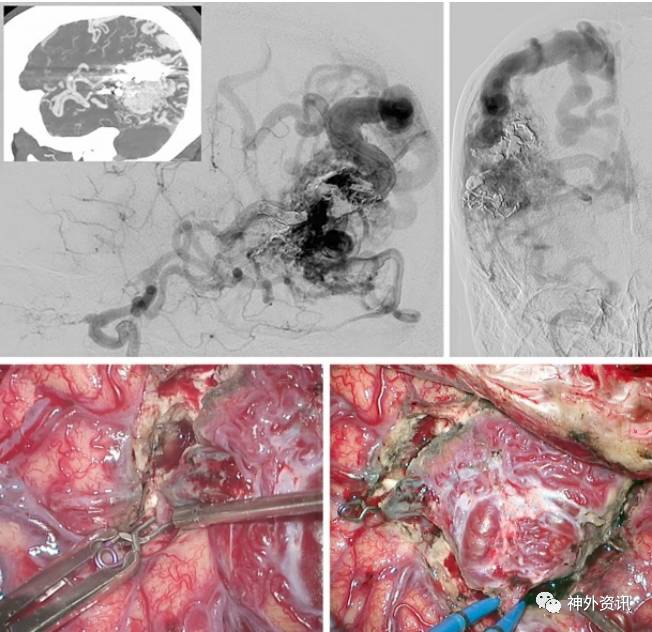

图5. 右侧颞顶叶外侧面大型、复杂AVMs(侧位和前后位的ICA脑血管造影-上图)。MCA的供血分支(左下图)和P2来源的供血动脉夹闭后切断。临时阻断静脉(右下图)以明确病灶没有血供,之后进行AVMs的离断移除。

图6. 破裂的颞叶外侧面AVMs切除。注意粗大并动脉化的Labbe 静脉(第一行)。直切口开颅形成颞部骨瓣,经脑沟入路确认MCA远端粗大的供血血管(第二行)。这个MCA分支是从病灶边缘路过的血管,沿着它分出许多AVMs的供养血管。病灶恰位于此“过路动脉”的上方,当此动脉被轮廓化后,病灶也即切除 (最后一行)。可以看到切除完成后Labbe静脉颜色变深。保存此过路动脉对于避免远端缺血是很重要的。